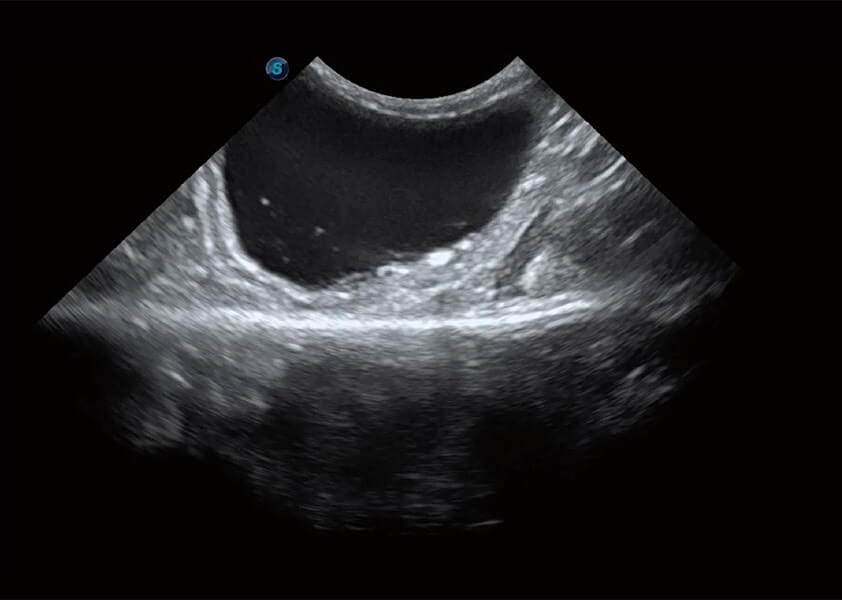

ProPet 60 作為一款高端臺式動物超聲設(shè)備,為動物醫(yī)生的日常診斷提供了一系列貼合動物臨床需求、解決臨床實際問題的高級成像功能。憑借全系列高清探頭,滿足醫(yī)生對腹部、心臟、生殖、淺表、肌骨等成像的所有需求,切實幫助您提升檢查效率,提高診斷信心。

動物是人類最親密的朋友和最值得信賴的伙伴。開立醫(yī)療也一直致力于探索動物專用的超聲影像解決方案。 全新推出的ProPet系列,是開立在動物超聲影像智能化、專業(yè)化、精準(zhǔn)化的一次跨越式革新。動物不能用言語來表述自己的不適,通過超聲影像,ProPet系列搭建了動物醫(yī)生與不同物種溝通的“橋梁”,為動物醫(yī)生注入了“治愈之力”。